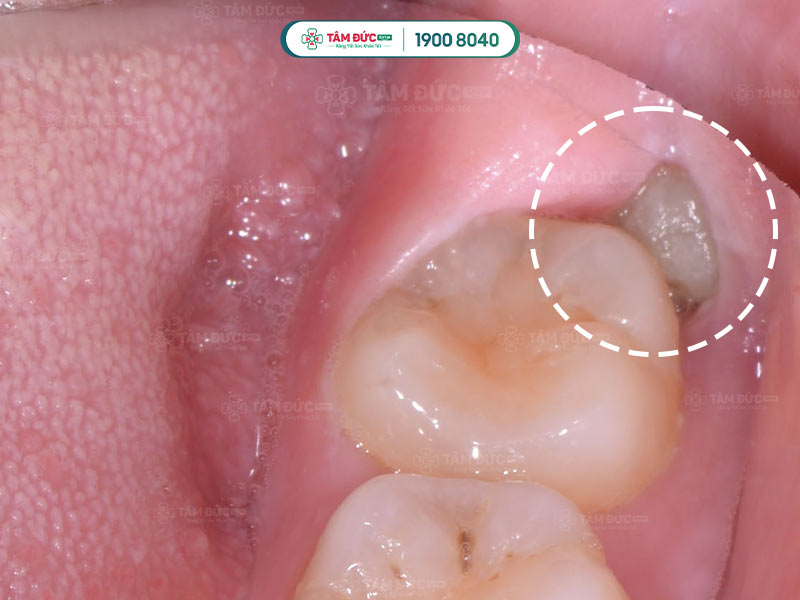

3.4. Xuất hiện đốm trắng sâu phía trong hàm

Những đốm trắng xuất hiện phía sau những chiếc răng cuối cùng chính là phần trên của răng khôn đang mọc lên xuyên qua nướu.

Răng khôn không còn đủ chỗ mọc